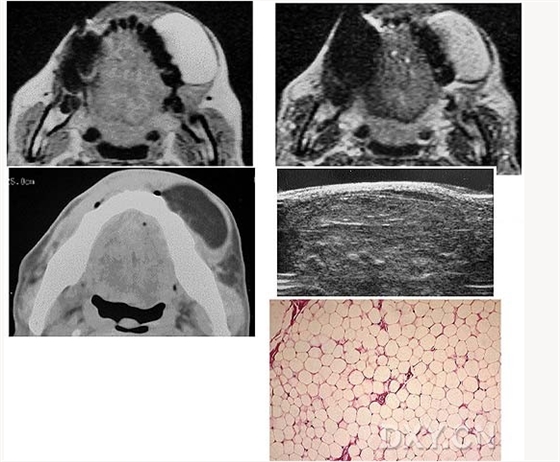

脂肪瘤